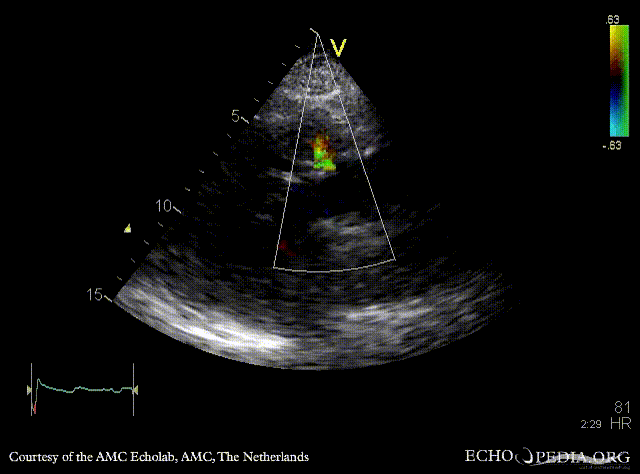

Fistula from ascending aorta to the right ventricle

A3CH: color doppler, fistula from ascending aorta to the right ventricle